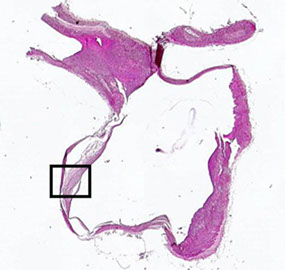

2) Brain Contusion/Laceration: Contusion/laceration injury of the brain results from direct contact at the site of impact and/or from relative movement of the brain inside the skull, related to acceleration/deceleration of the head. Contusion is a "bruise" of the brain. Laceration results from more severe tissue injury than contusion and is associated with tearing of the pial surface. The most superficial portions of the brain (crests of the gyri) undergo necrosis with eventual gliosis of adjacent tissue.

- contusions typically develop along crest of gyrus, and infarcts are centered at the base

Brain contusion